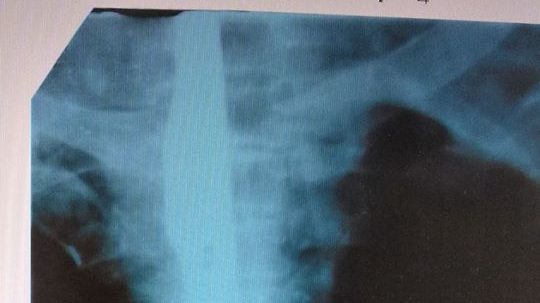

В городе Каменка-Днепровская к врачам обратился мужчина, который жаловался на сильную боль в горле, нарушения функций глотания и кровохарканье в течение 9 дней.

После того, как мужчине сделали рентген, оказалось, что у него в пищеводе находится… нож. Транспортировка больного грозила бы причинением тяжелых внутренних повреждений и массивного кровотечения, было принято решение оперировать на месте. Спасением жизни человека занималась команда из 15 медицинских работников, пишет газета «Знамя труда».

После проведения операции, нож был изъят. К сожалению, несмотря на все старания врачей в дальнейшем, человек умер. Каким образом нож попал в пищевод мужчины — выяснят правоохранители.